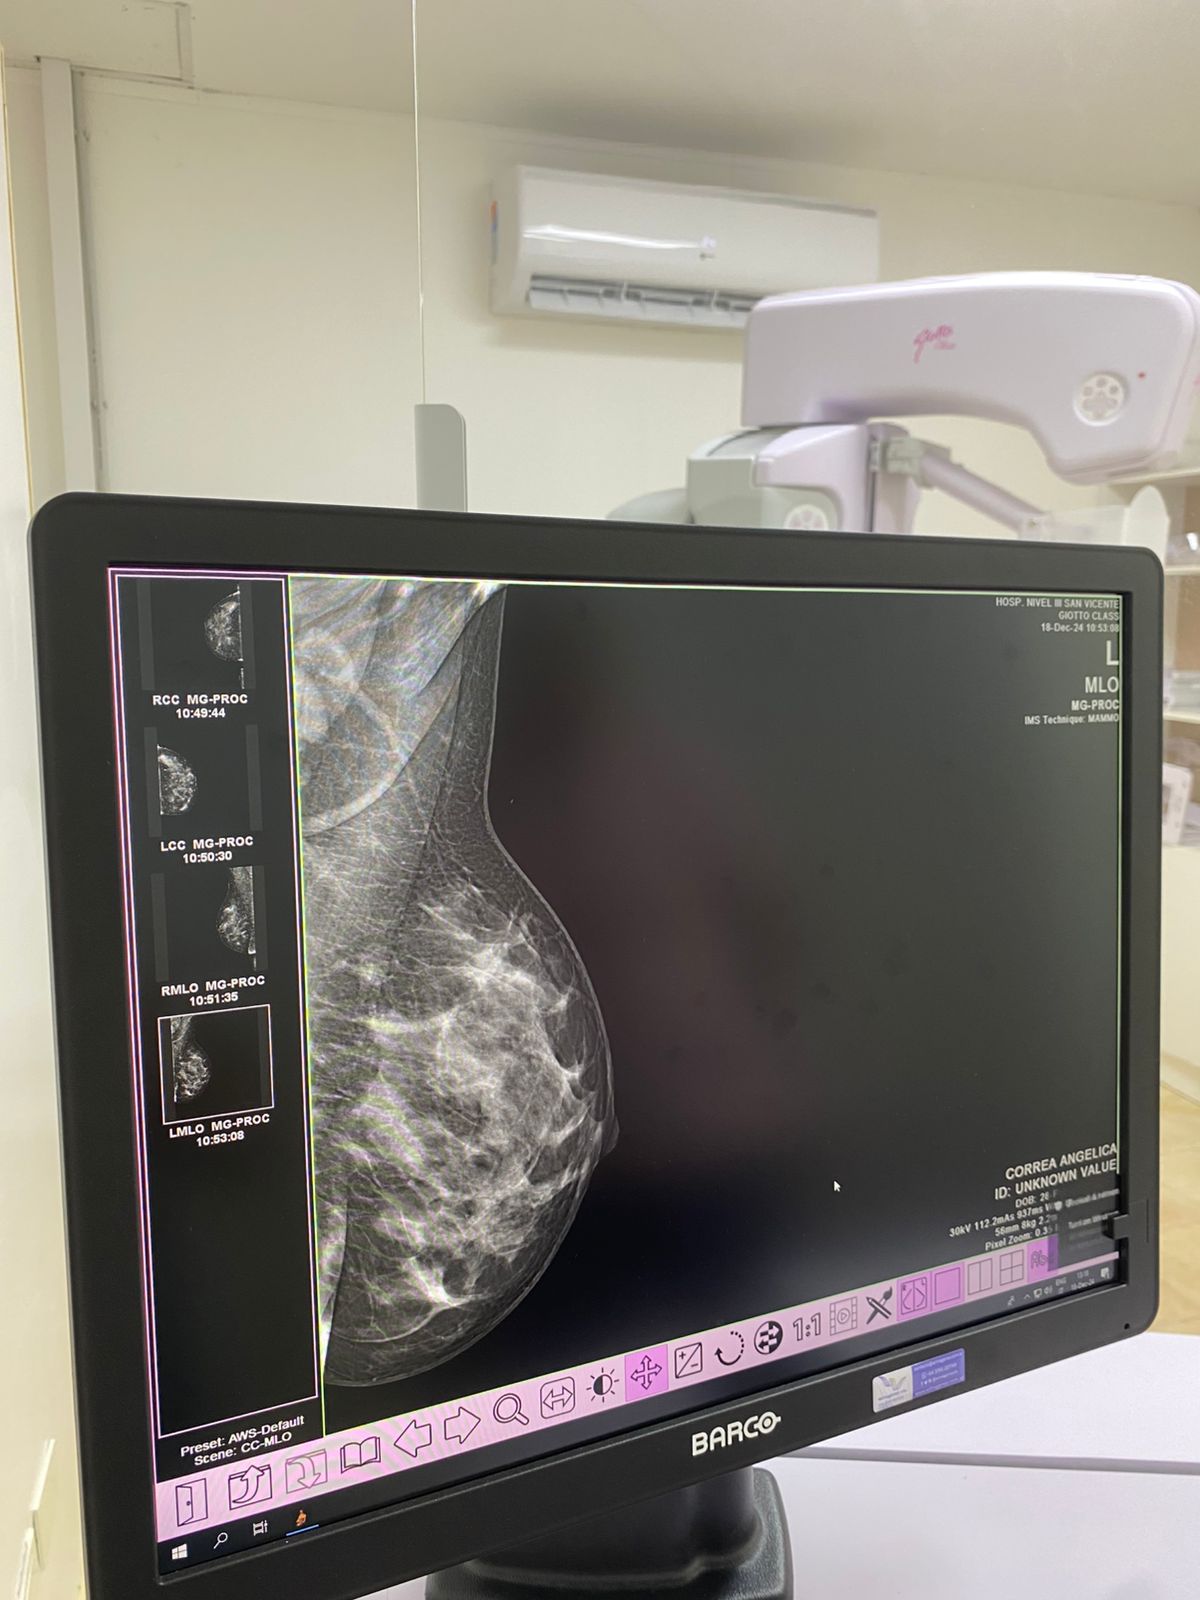

San Vicente. A tres meses la puesta en funcionamiento del Servicio de Mamografía en el Hospital de Nivel III de San Vicente ya se realizaron 195 estudios mamográficos.

El equipo mamográfico digital de última generación se puso en marcha a fines de marzo de este año, con claro objetivo de mejorar la calidad en la atención.